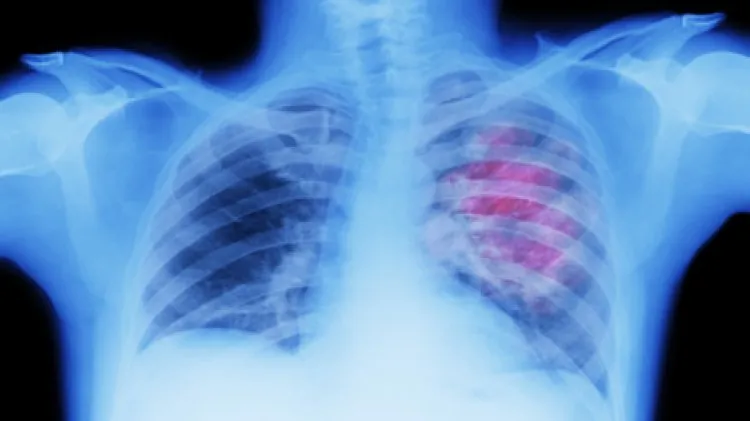

على الرغم من أن سرطان الرئة لا يظهر عادة أعراضا في المراحل المبكرة، فقد تظهر العلامات التحذيرية مع تقدم الحالة.

وعندما تفكر في سرطان الرئة، قد تتبادر إلى ذهنك أعراض مثل السعال أو ضيق التنفس. وبصرف النظر عن رئتيك وصدرك، هناك منطقة أخرى يمكن أن تشير إلى الحالة - الأصابع. وشارك مركز أبحاث السرطان في المملكة المتحدة أن إحدى العلامات التي يمكن أن تكون أحد أعراض سرطان الرئة هي تعجر الأصابع.

ويمكن رصد هذه الأعراض الخاصة بين المرضى الذين يعانون من مشاكل في الرئة والقلب، بما في ذلك سرطان الرئة. ومن اللون الخفيف إلى المنحنى، هناك عدد قليل من العلامات الدالة على تعجر الأصابع.